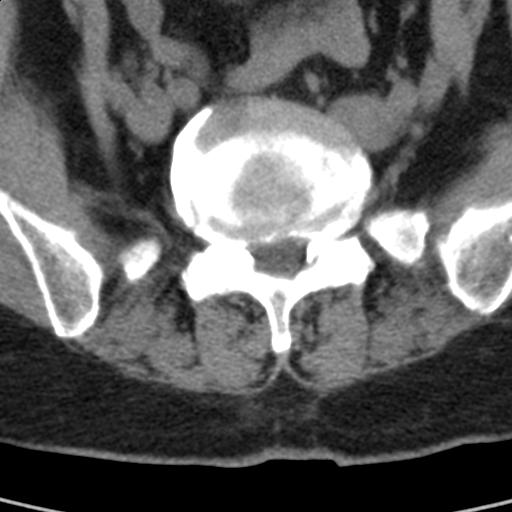

患者;女性;左下肢疼痛。

l5s1显示椎间盘突出,椎体边缘骨质增生,双侧黄韧带钙化。(请上传骨窗)

l5s1显示椎间盘突出,椎体边缘骨质增生,双侧黄韧带钙化 ,两侧椎小关节肥大,关节面硬化,关节间隙变窄,提示:椎小关节综合症

双侧的侧隐窝有狭窄。

我认为应该考虑为:l5s1椎间盘膨出,余(椎小关节退变、黄韧带钙化、椎间孔狭窄)与各位同行无异议。

l5s1显示椎间盘膨出,突出,椎体边缘骨质增生向后压迫硬膜囊,双侧黄韧带钙化,小关节面综合征

l5s1椎间盘向后脱出使脊膜囊受压,椎体边缘骨质增生,双侧黄韧带钙化。l45椎间盘估计亦突出,为何未扫。